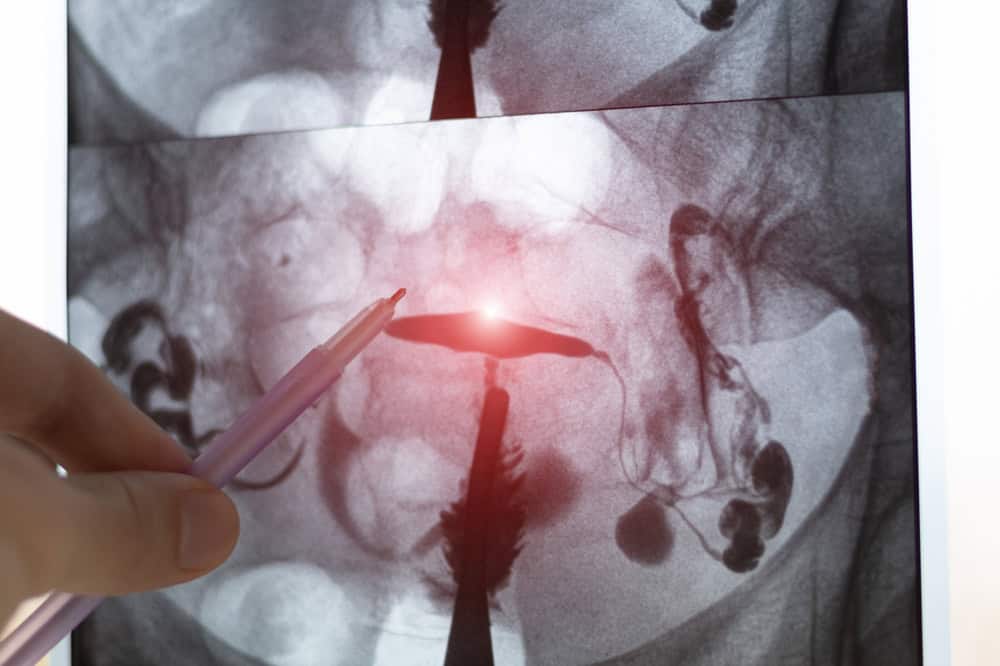

การตรวจสภาพท่อนำไข่และโพรงมดลูก

การตรวจสำหรับผู้ที่เคยมีประวัติการท้องนอกมดลูกโดยเฉพาะ ลดความเสี่ยงการเกิดซ้ำ ประกอบด้วย

- การฉีดสีท่อนำไข่ (HSG หรือ Hysterosalpingography) เพื่อดูว่าท่อนำไข่ข้างที่เหลือเปิดปกติหรือไม่

- การส่องกล้องผ่านทางช่องท้อง (Laparoscopy) เพื่อดูพังผืดหรือการอักเสบโดยตรง

- การส่องกล้องโพรงมดลูก (Hysteroscopy) เพื่อหาสาเหตุที่อาจทำให้ตัวอ่อนไม่ฝังตัว